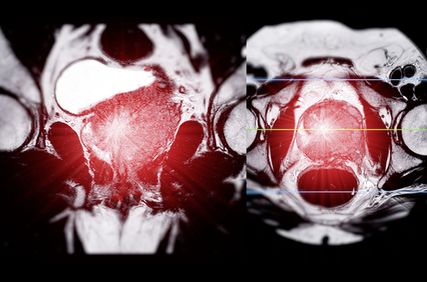

Wichtig zu beachten ist, dass in der EMBARK-Studie eine konventionelle und keine PSMA-basierte Bildgebung angewandt wurde. Wir wissen aus kürzlich publizierten Untersuchungen, dass in einer Population von Personen, die den EMBARK-Kriterien entsprachen, bei ca. 80% mit einer PSMA-PET-Bildgebung eine Rezidivlokalisation möglich ist:2

-

ca. 25% Lokalrezidiv

ca. 50% regionäre Lymphknotenmetastasen

ca. 25% weiter entfernte Lymphknotenmetastasen

ca. 25% Knochenmetastasen und Kombinationen davon